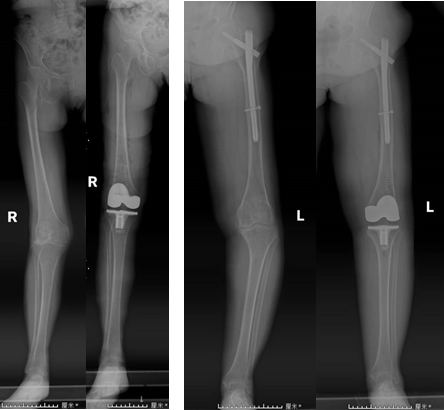

手術前后患者X線片對比

全膝關節(jié)手術定位系統(tǒng)(iKPAS)可用于初次或復雜全膝關節(jié)置換手術,在不開髓的情況下實現(xiàn)膝關節(jié)力線的定位,尤其針對股骨骨折內(nèi)固定物未取出的情況,優(yōu)勢更加明顯。